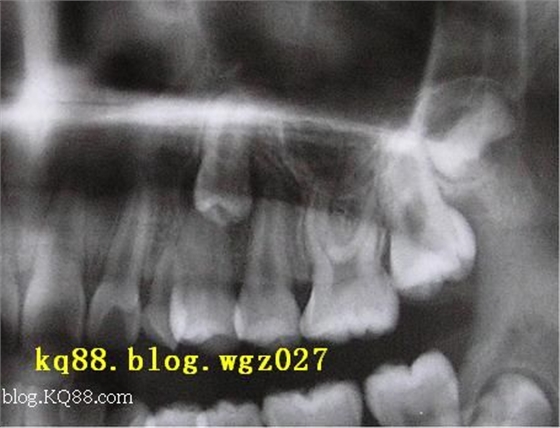

術前準備:常規(guī)矯治,開展或維持埋伏牙的有效間隙。拍攝X線牙片,咬合片及用手指觸診定位,確定開窗部位準備粘接附件,設定牽引方法。

術前準備:常規(guī)矯治,開展或維持埋伏牙的有效間隙。拍攝X線牙片、咬合片及觸診確定手術進路,附件用0.014″直徑正畸鋼絲,底部做成約1.5mm直徑的小圈,與鋼絲成90°、游離端充分退火(使之柔軟易于彎曲),備用。